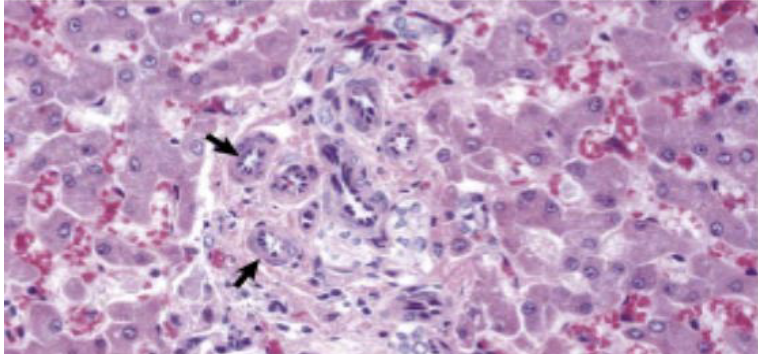

what does the image show?

amyloidosis